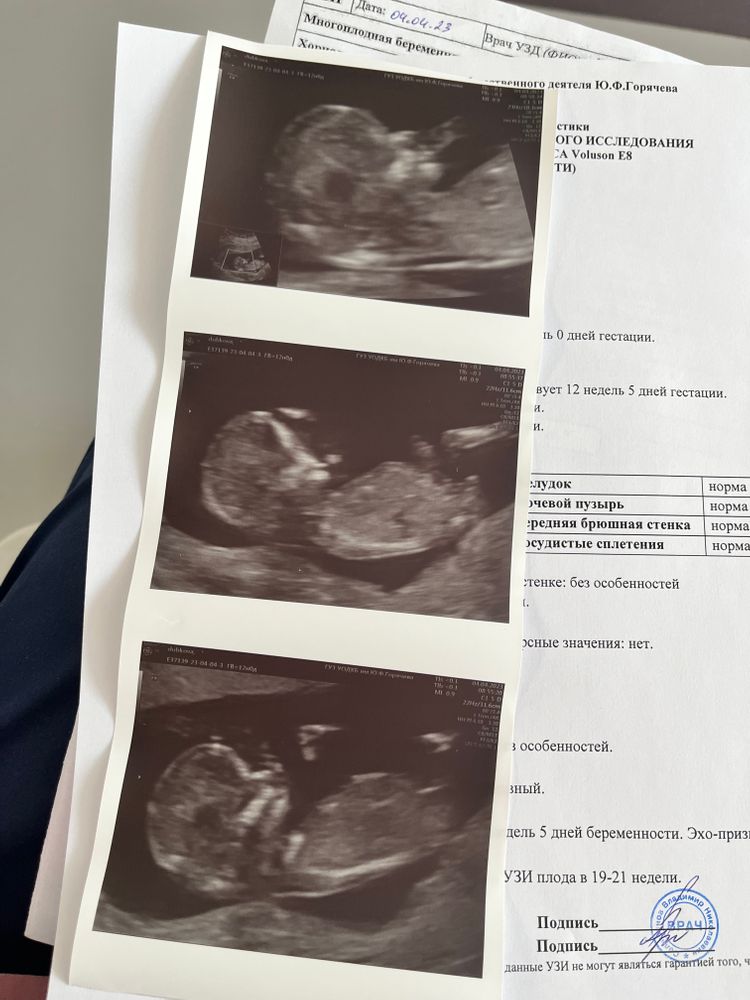

Первый скрининг, никак не отойду от эмоций ☺️🙈

Изображение

Все хорошо, единственное, тонус. Но живот не болит, хожу, когда много, болит поясница и всё. А так в целом, все супер, малыш опережает на 5 дней, предварительно